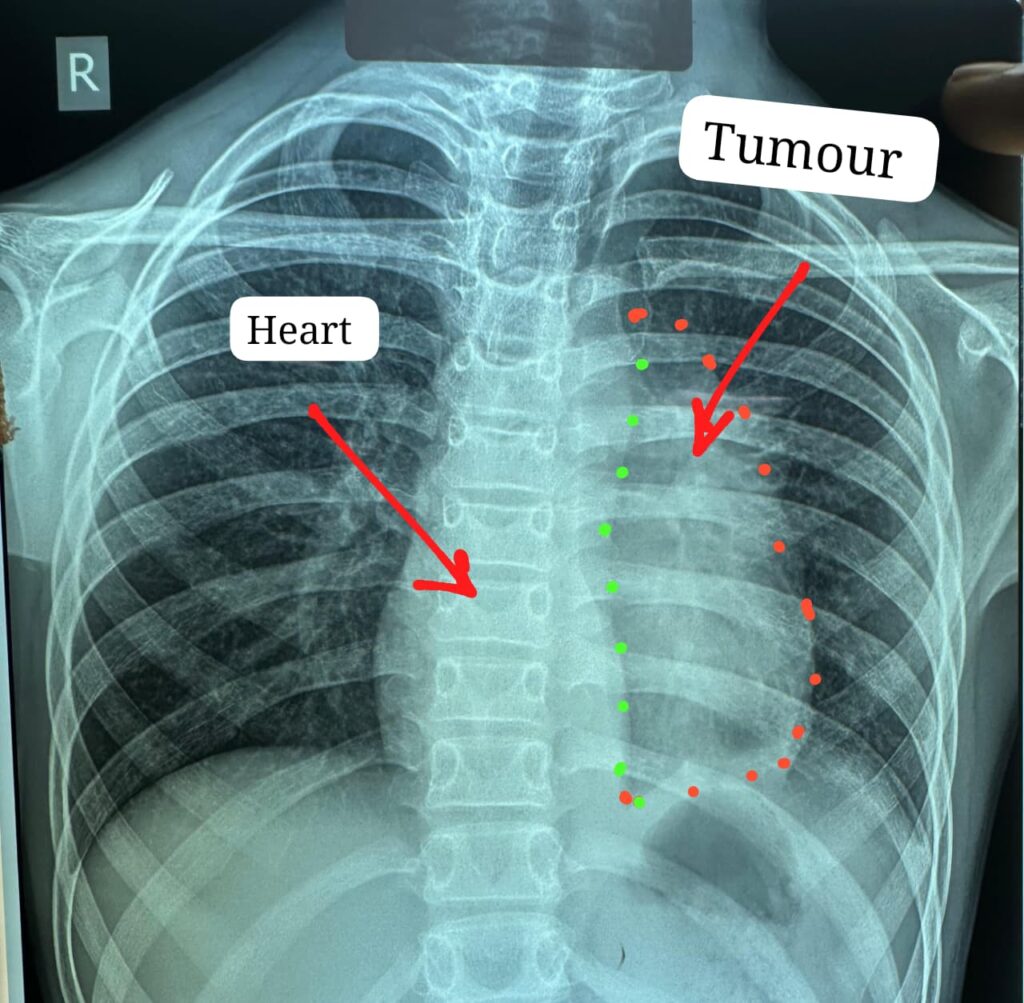

डॉक्टरों के अनुसार यह ट्यूमर सामान्यतः 40 से 60 वर्ष के लोगों में पाया जाता है और बच्चों में इसका मिलना अत्यंत दुर्लभ है। यह ट्यूमर हृदय, पेरिकार्डियम, फ्रेनिक नर्व महाधमनी (एओर्टा), मुख्य पल्मोनरी आर्टरी, लेफ्ट एट्रियम और फेफड़े से चिपका हुआ था। ऐसे मामलों में ट्यूमर को पूरी तरह निकाल पाना (आर-0 रिसेक्शन) लगभग असंभव माना जाता है, लेकिन अस्पताल में उपलब्ध हार्ट-लंग मशीन की मदद से यह संभव हो पाया।

मुख्य ट्यूमर के अलावा फेफड़े की प्लूरल कैविटी में फैले तीन अन्य सैटेलाइट ट्यूमर को भी सावधानीपूर्वक निकाला गया, ताकि भविष्य में कैंसर दोबारा फैलने की संभावना न रहे। निकाले गए ट्यूमर का आकार लगभग 12×8 सेंटीमीटर और वजन करीब 400 ग्राम था।

चांपा निवासी कक्षा छठवीं में पढ़ने वाले इस बच्चे को करीब छह महीने से छाती में दर्द, भारीपन और सांस फूलने की शिकायत थी। जांच में पता चला कि उसके सीने में बड़ा ट्यूमर है, जो हृदय और मुख्य धमनियों से चिपका हुआ है। प्रदेश के कई अस्पतालों में ऑपरेशन से मना किए जाने के बाद मरीज को अम्बेडकर अस्पताल भेजा गया।